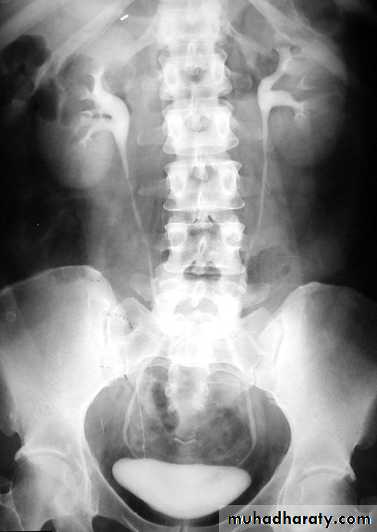

KUB

Multiple bilateral renal stonesStaghorn stone needs PCNL